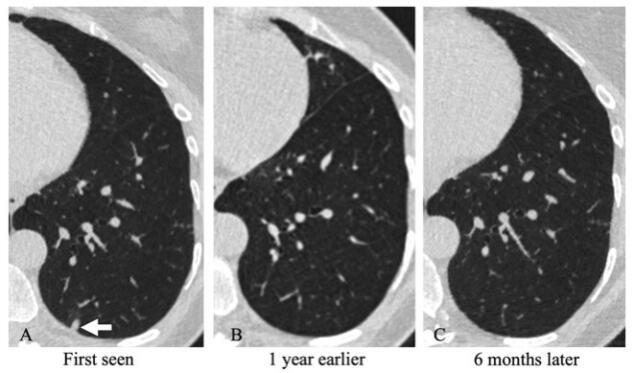

肋胸膜附着非钙化结节有两个特点,第一它的位置位于肋胸膜上,这一点从胸部CT中可以较为明显的看到。第二点一般多为实性结节,但这种实性结节一般不包括有条索延伸到肋骨胸膜的结节。

图片肋胸膜附着非钙化结节